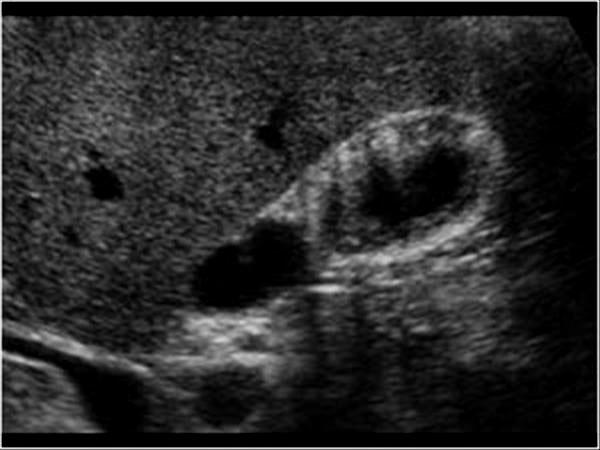

Mirizzi SYndrome

impacted stone in the cystic duct or GB neck

presence of two tubular structures representing the bile duct above the level of the cystic duct

Mirizzi SYndrome

impacted stone in the cystic duct or GB neck

presence of two tubular structures representing the bile duct above the level of the cystic duct